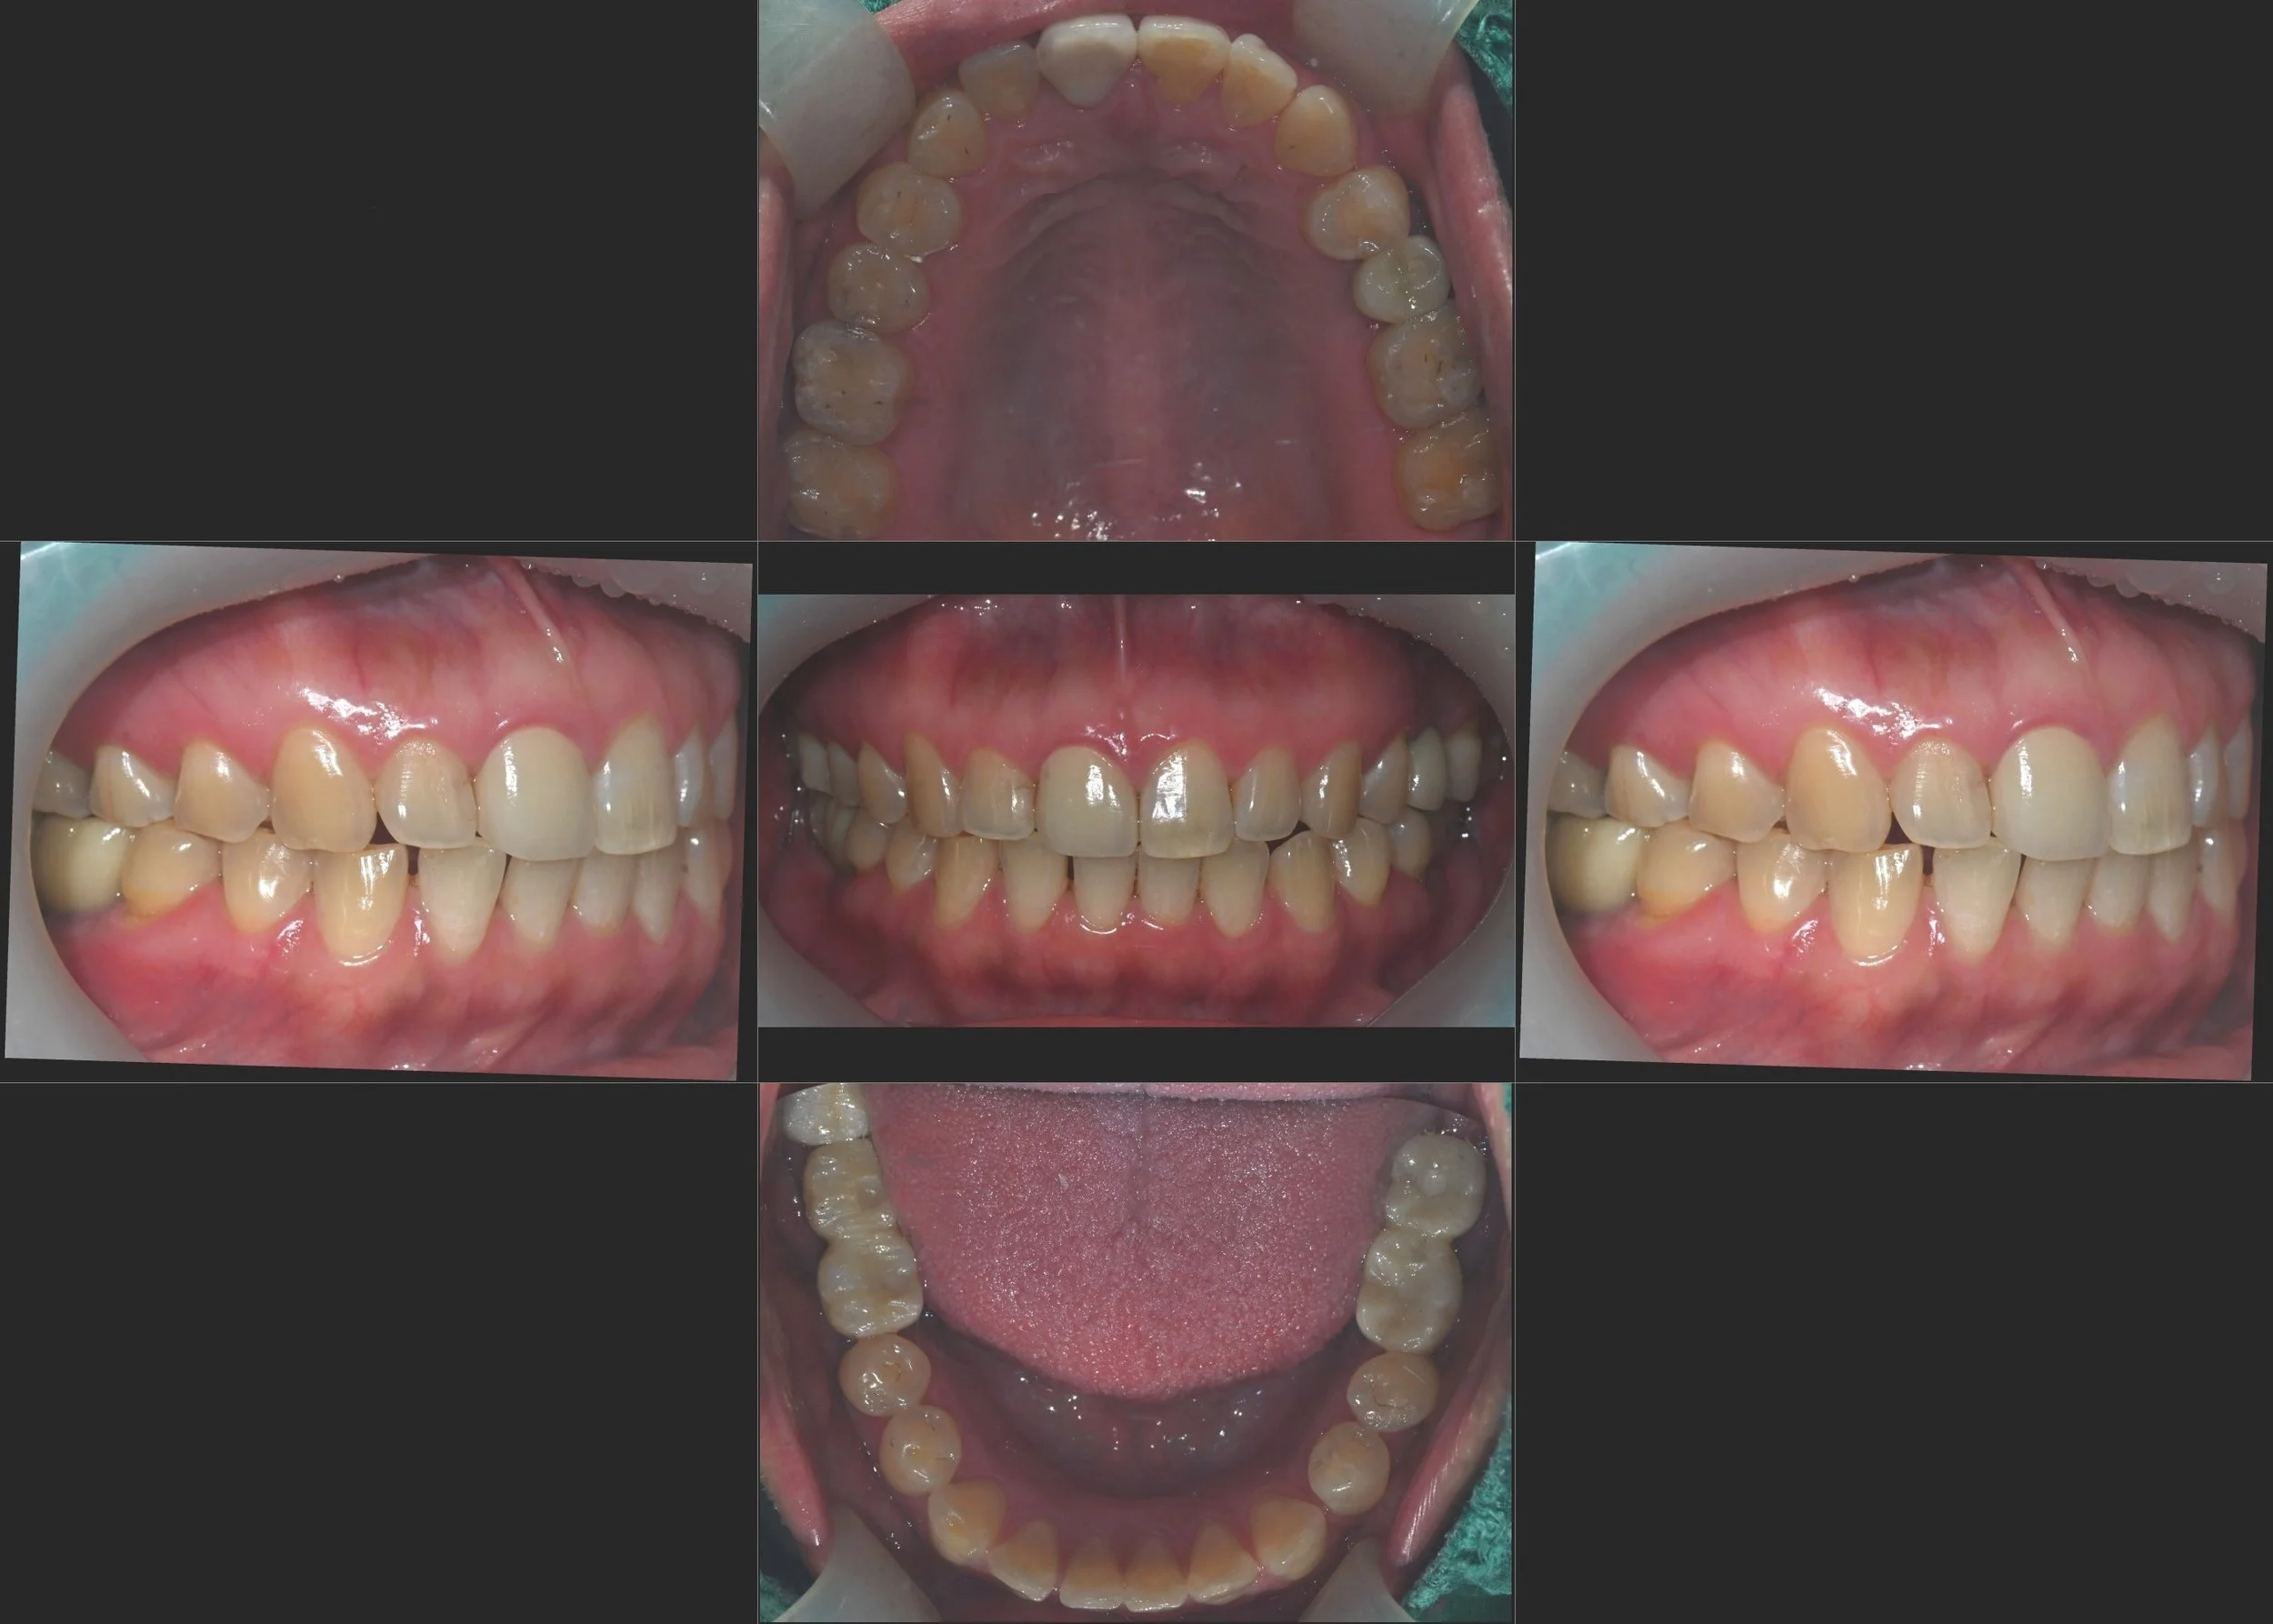

INTRA ORAL - AFTER

2. Slight VDO Elevation: Using provisional restorations, the vertical dimension was slightly elevated. This was critical to re-establish a harmonious occlusal curve and to compensate for the previous supra-eruption of the upper teeth.

3. Extended Adaptation Phase: A critical component of this case was the multi-month adaptation period. The patient was monitored closely while wearing temporary restorations to verify that the TMJ symptoms had fully subsided and that the new mandibular position was stable and reproducible.

4. Final Delivery: Once functional comfort was confirmed, the final restorations were delivered. The new occlusal scheme provides balanced bilateral support, protecting the joints and ensuring a stable, centered bite.

The patient achieved complete relief from her TMJ symptoms and regained full masticatory function with a stable, harmonized occlusion.